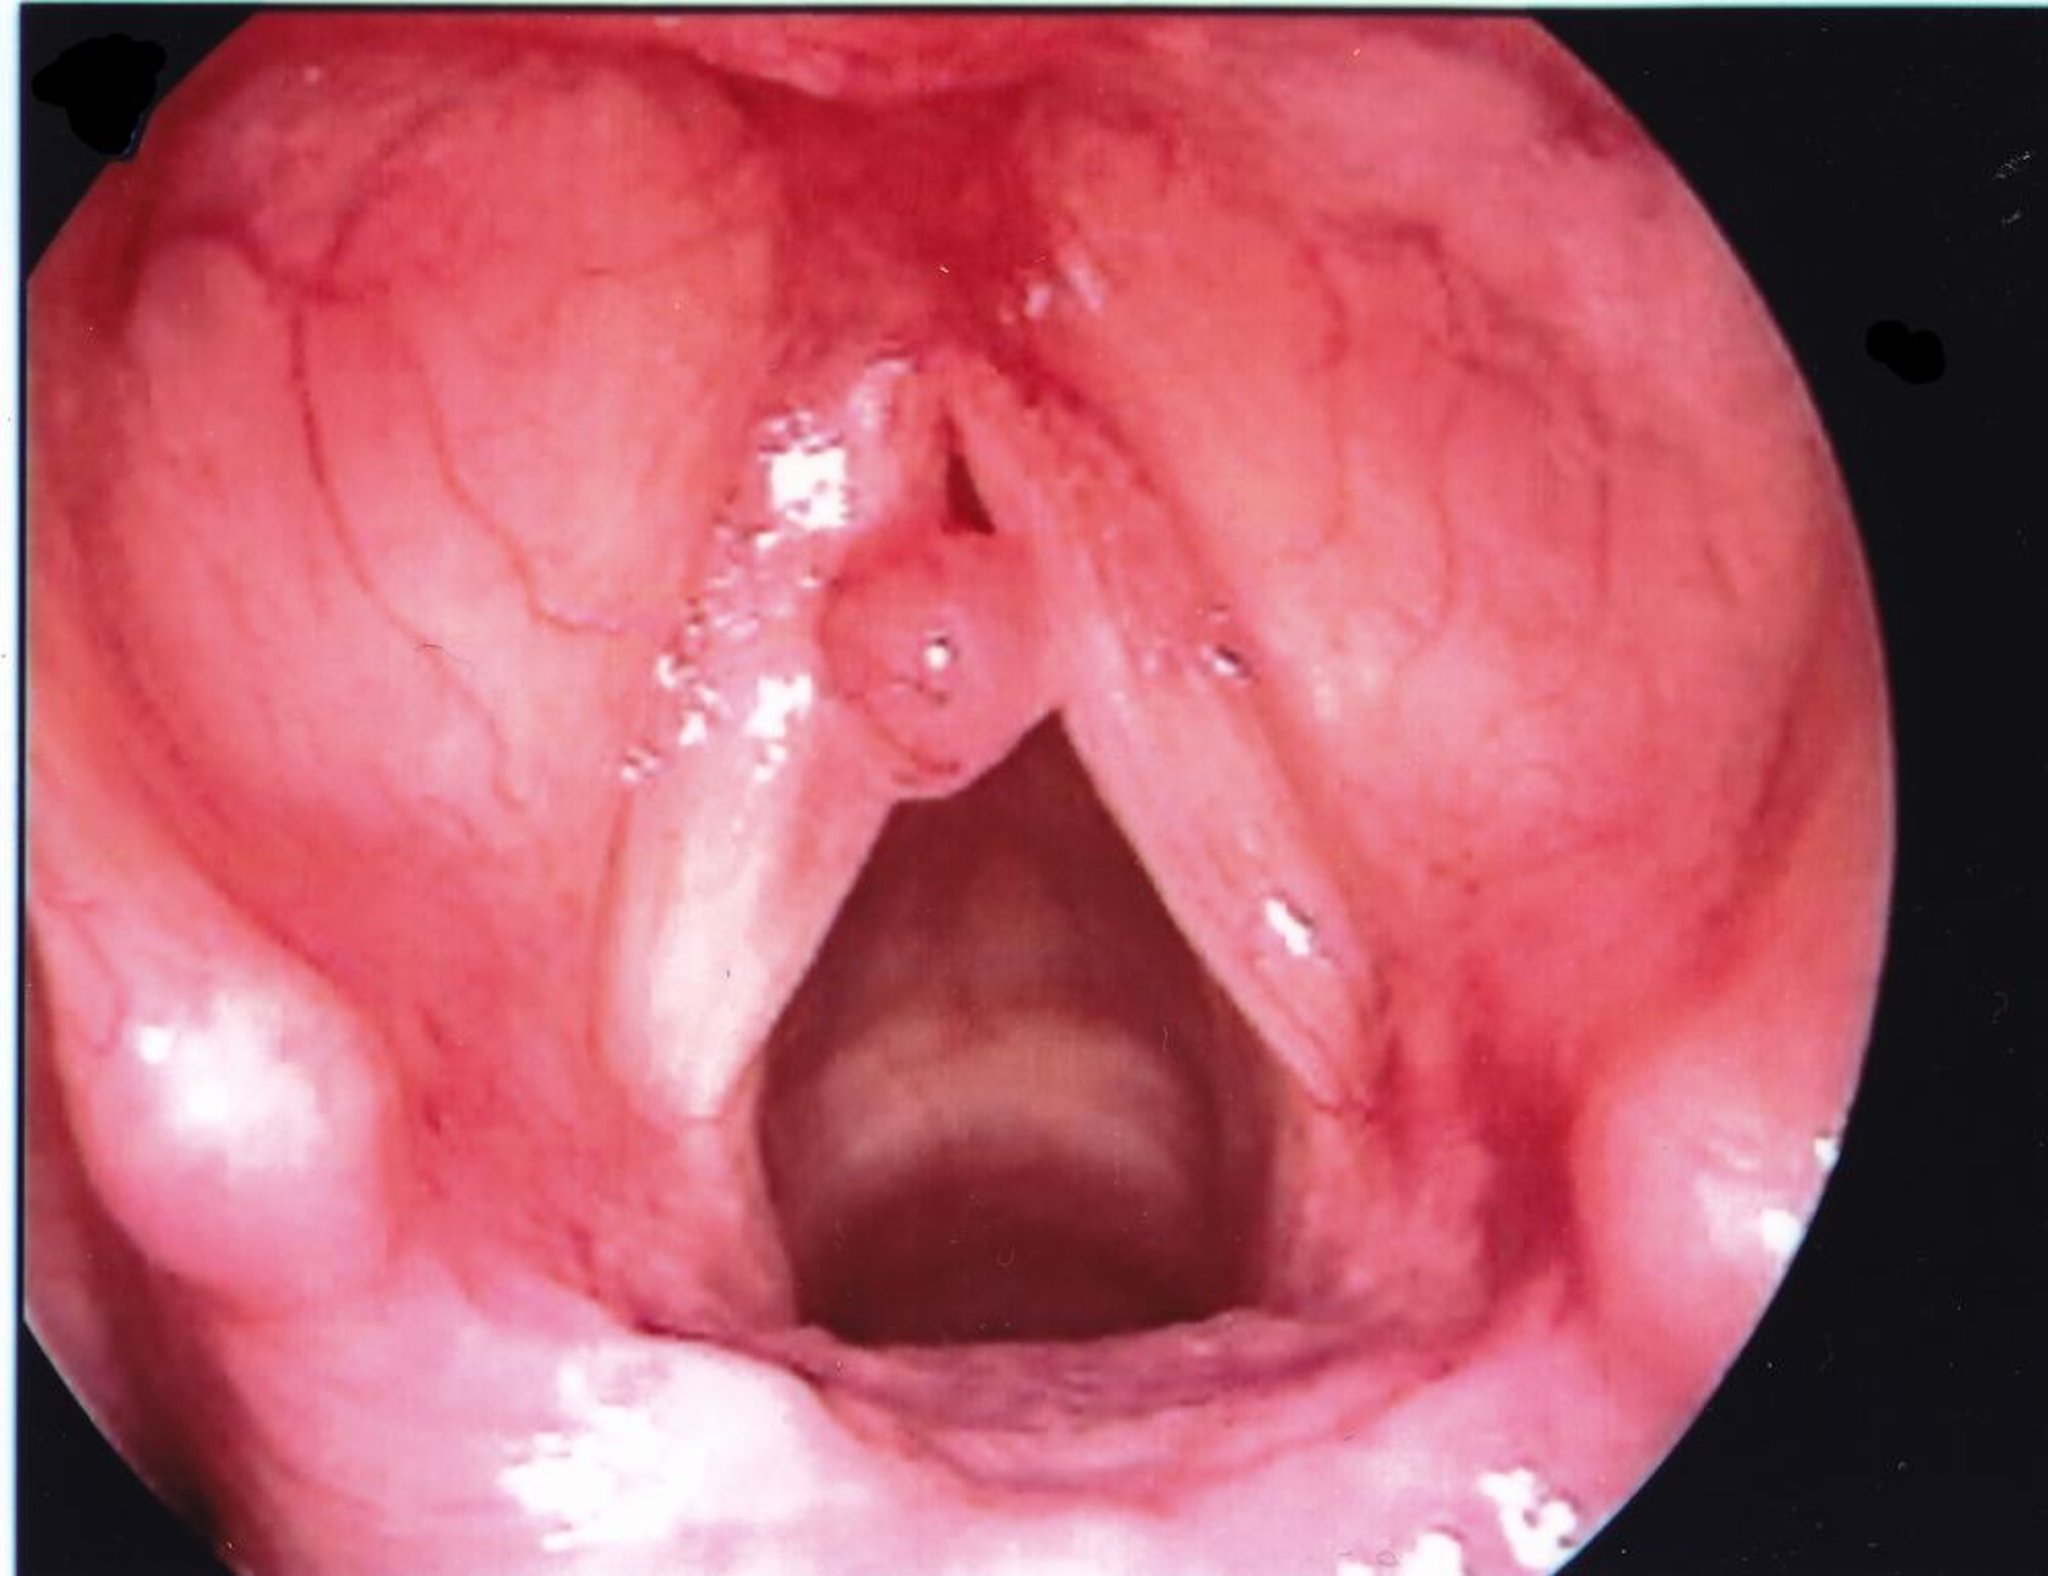

Stimmbandpolyp

Ein Stimmbandpolyp erscheint in der Regel einseitig und ist größer als ein Knoten.

Abbildung zur Verfügung gestellt von Eiji Yanagisawa, MD.